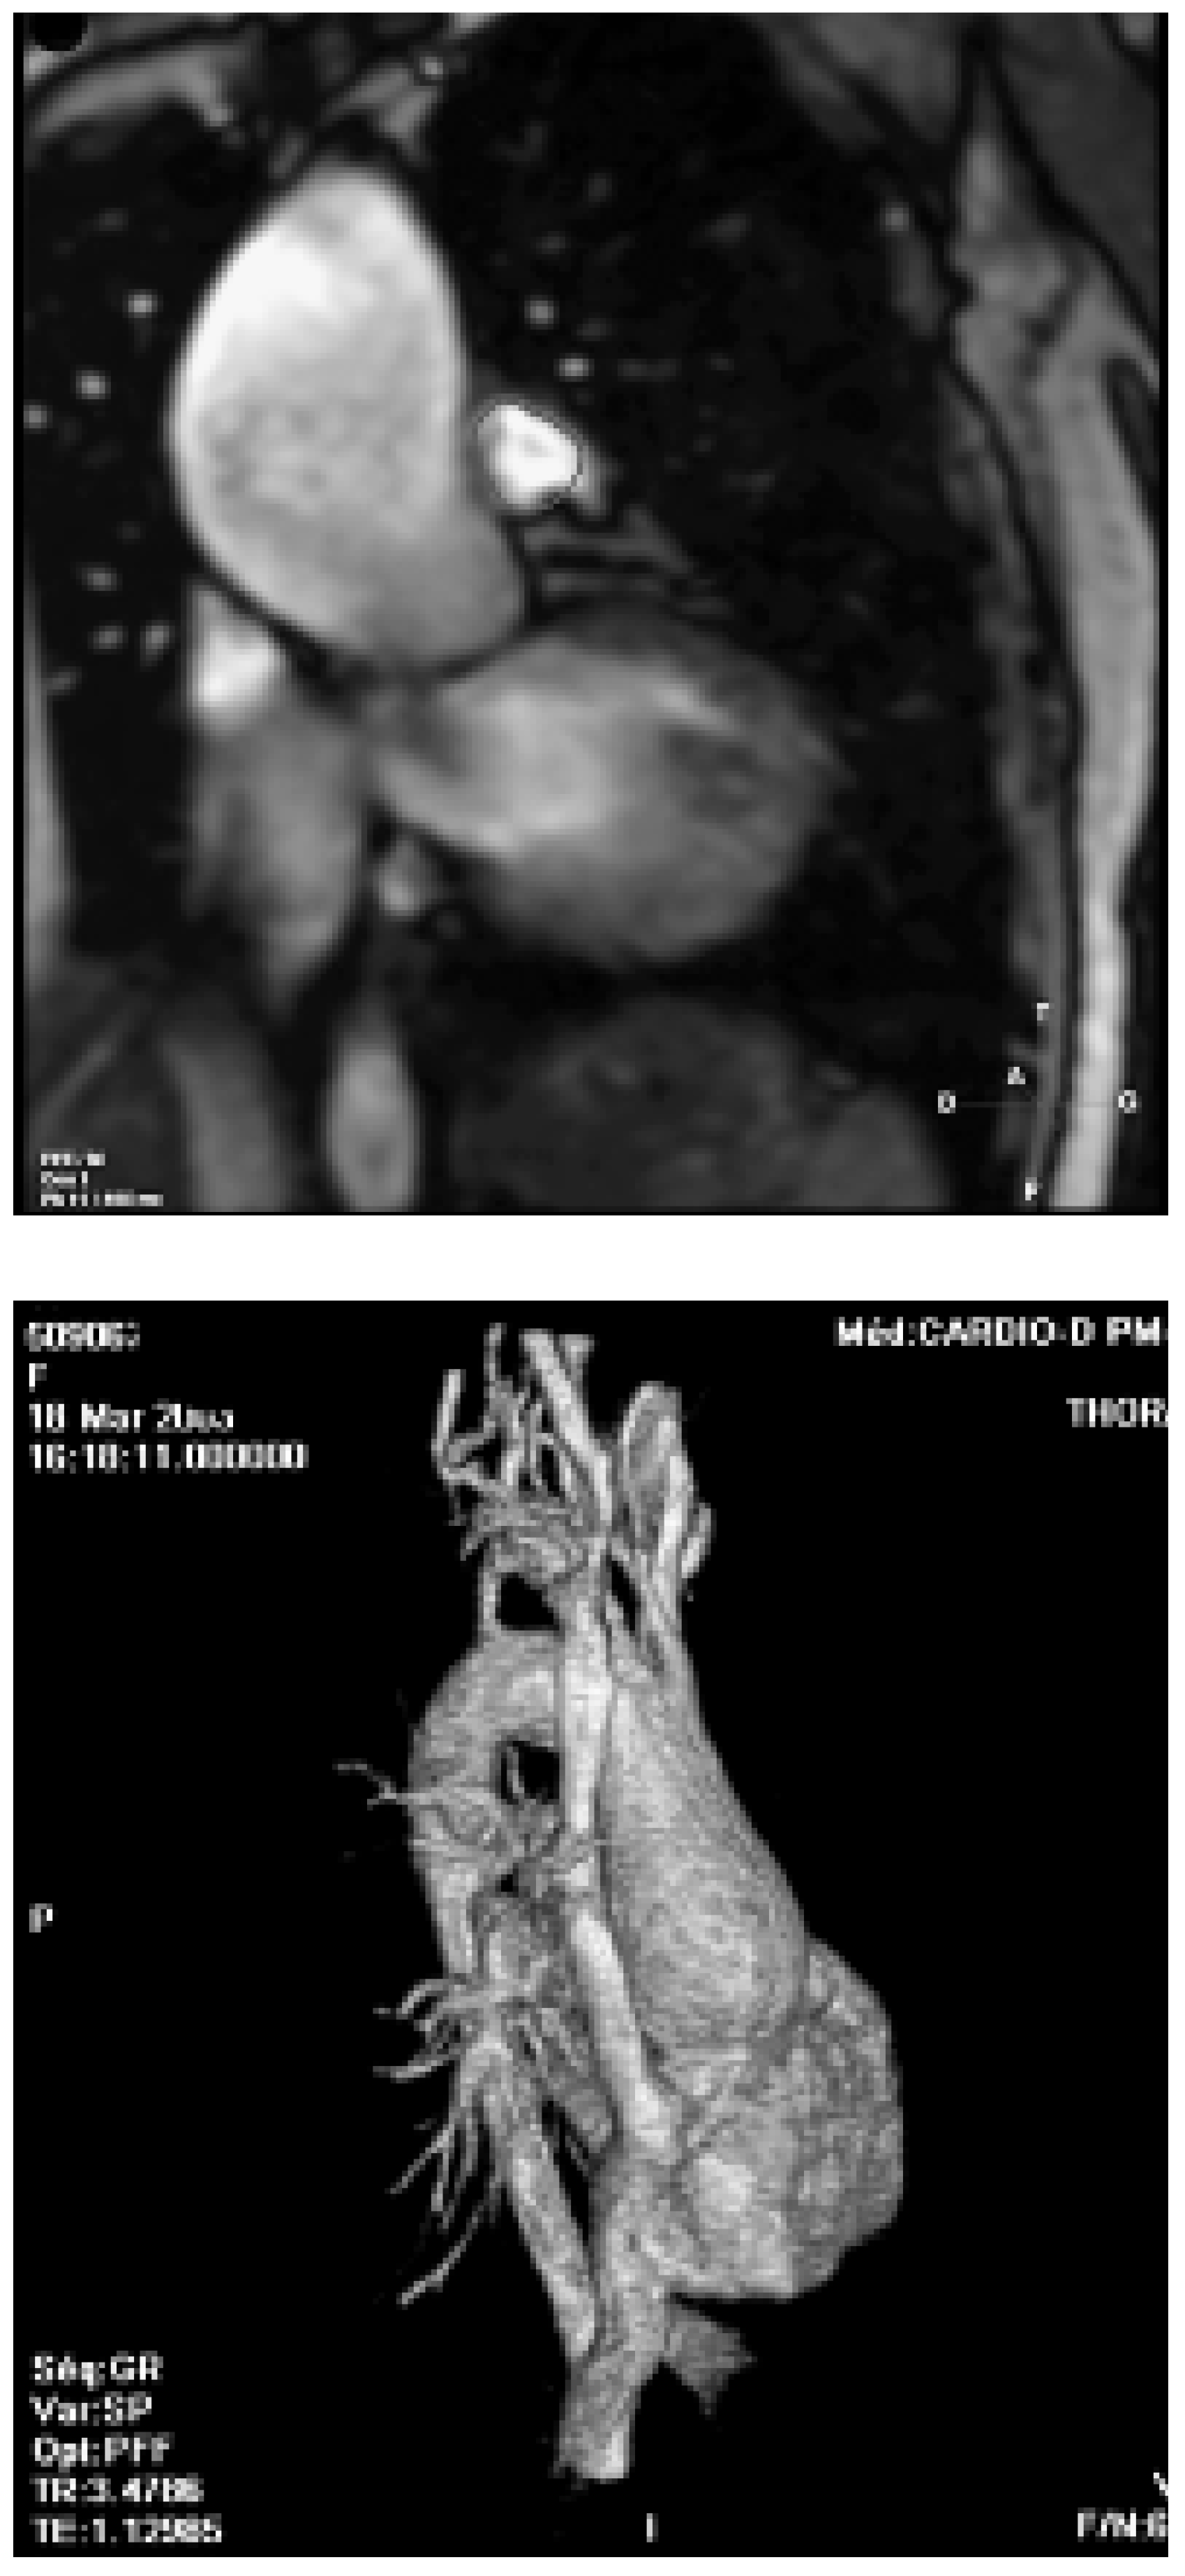

- Vliegen, H.W.; van Straten, A.; de Roos, A.; et al. Magnetic resonance imaging to assess the hemodynamic effects of pulmonary valve replacement in adults late after repair of tetralogy of Fallot. Circulation 2002, 106, 1703–1707. [Google Scholar] [CrossRef]

- Davlouros, P.A.; Kilner, P.J.; Hornung, T.S.; et al. Right ventricular function in adults with repaired tetralogy of Fallot assessed with cardiovascular magnetic resonance imaging: Detrimental role of right ventricular outflow aneurysms or akinesia and adverse right-to-left ventricular interaction. J Am Coll Cardiol. 2002, 40, 2044–2052. [Google Scholar] [CrossRef] [PubMed]

- Geva, T.; Sandweiss, B.M.; Gauvreau, K.; et al. Factors associated with impaired clinical status in long-term survivors of tetralogy of Fallot repair evaluated by magnetic resonance imaging. J Am Coll Cardiol. 2004, 43, 1068–1074. [Google Scholar] [CrossRef] [PubMed]